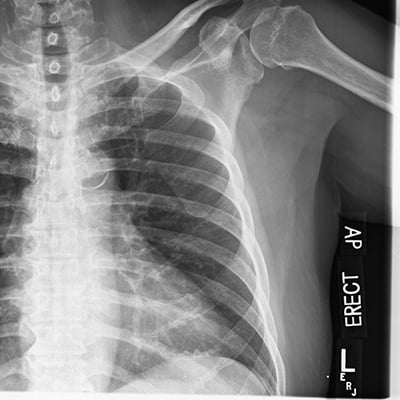

This module will help you achieve optimal images when performing elbow, humerus, shoulder, and scapula examinations. Patient preparation and positioning are discussed, as well as technical settings and patient instructions. Descriptions and images of the expected anatomical structures are included, as well as image evaluation criteria.